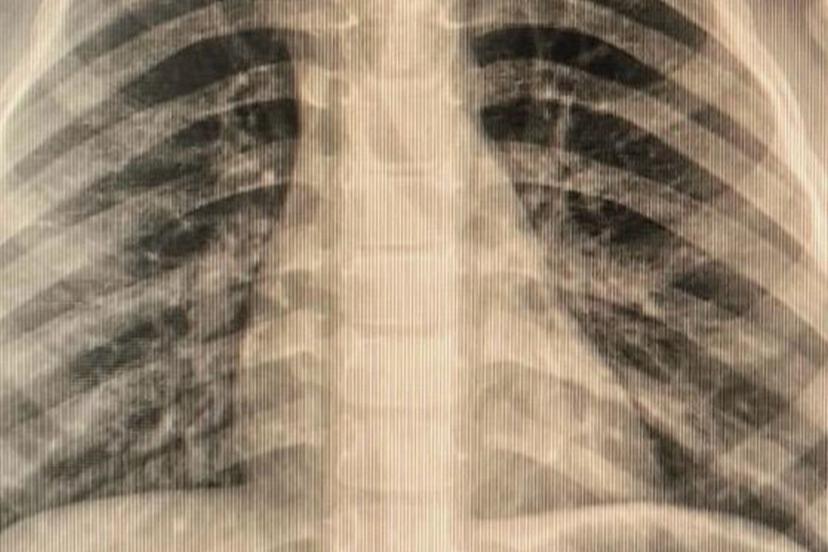

Çocuklarda sık karşılaşılan risklere değinen Özkaya "Günlük hayatta çocuklarda sık karşılaşılan yabancı cisim yutulması, kimyasal madde içilmesi ve solunum yollarına yabancı cisim kaçması önemli sağlık sorunları arasında yer almaktadır. Özellikle ilk üç yaşındaki çocuklar, yerde buldukları nesneleri ağızlarına götürme eğilimindedir. Madeni paralar, disk piller, iğneler ve küçük oyuncak parçaları çocuklar tarafından yutulabilmekte; bu maddeler yemek borusuna ya da solunum yollarına kaçabilmektedir. Bu tür durumlarda ailelerin olaya şahit olmaları hâlinde çocuğun ağzını kontrol etmeleri, yutma şüphesi varsa vakit kaybetmeden en yakın sağlık kuruluşuna başvurmaları gerekmektedir." dedi.